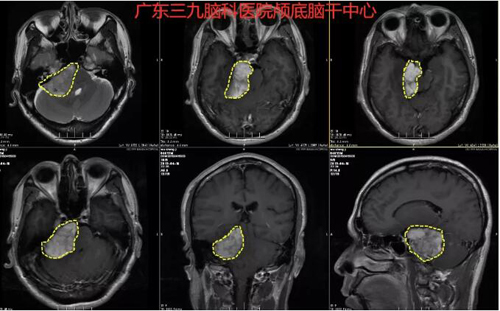

图2:术前MR示右侧跨中后颅窝示团块状不匀长T1长T2异常信号影,FLAIR序列呈稍高信号影,其内间杂数个细小线样血管影,范围约4.6cm×3.0cm×4.1cm,增强后呈不均匀明显强化,并右侧听神经根增粗强化,邻近脑干、右侧桥臂及右侧小脑半球受压移位。左侧额叶皮层下白质内及双侧放射冠区示斑点状等T1长T2异常信号影,FLAIR序列呈高信号。四脑室受压变窄,幕上脑室系统未见扩张,脑沟、脑裂及脑池未见增宽,中线结构居中